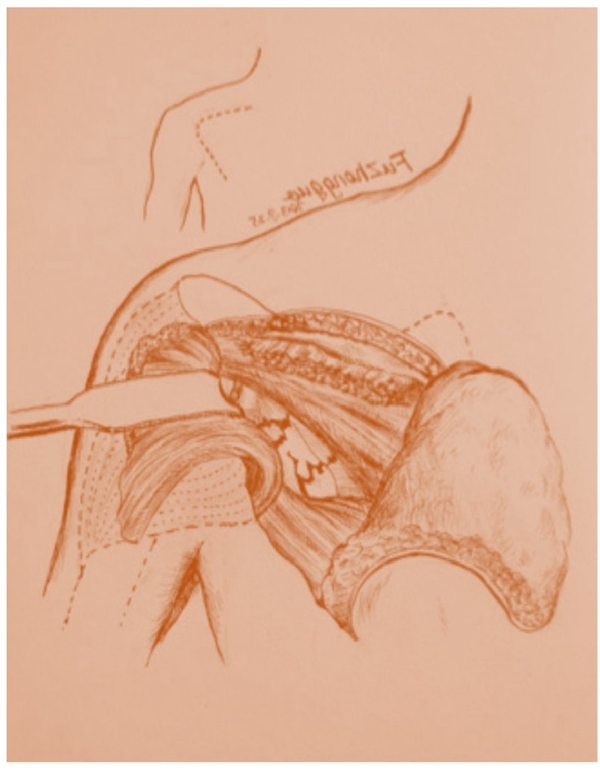

这一入路适用于仅累及肩胛盂、肩胛颈的IdebergⅠ-Ⅲ型骨折,术中通过分离冈下肌与小圆肌显露骨折区域。这是一种安全、可靠的手术入路,切口短、创伤小,软组织剥离范围小,暴露直接,节约手术时间,可以使骨折获得满意的复位以及牢靠的固定(图1)。

图1 肩胛骨骨折背侧小切口